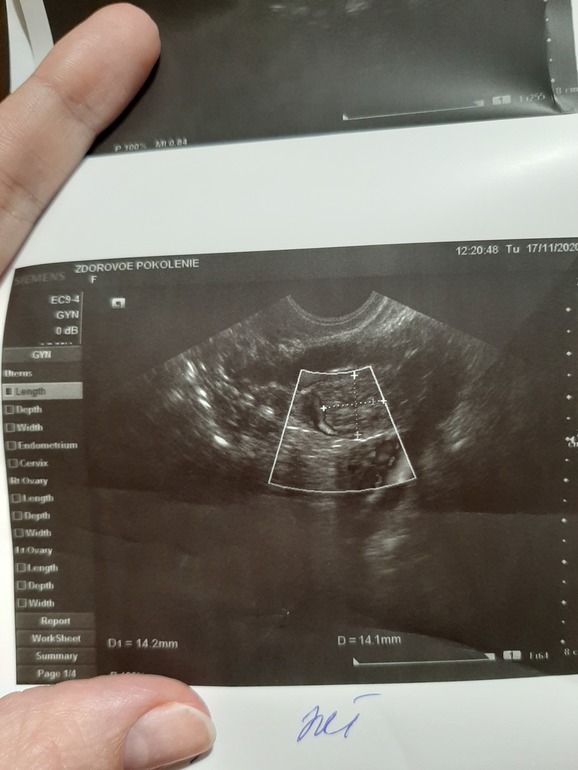

вот узи

Ооо у Вас шикарное у меня реально маленькое

Дай Бог!🙏😏но весь инет перерыла с таким желтым телом не может быть. Но на ББ видела с 16 и 17 Б

И кстати эндометрий у вас хороший, у меня всего 10мм

Эндометрий не однослойный, а однородный, это норма. Трехслойным он должен быть в первой фазе. А размер ЖТ никак не влияет на количество вырабатываемого прогестерона

Угасание ЖТ определяют по степени визуализации и ЦДК (кровотоку по контуру), в заключении не написано по этому поводу ничего, поэтому сказать нельзя. По эндометрию тоже можно определить, когда пойдут месячные (линия смыкания лепестков перестаёт визуализироваться)